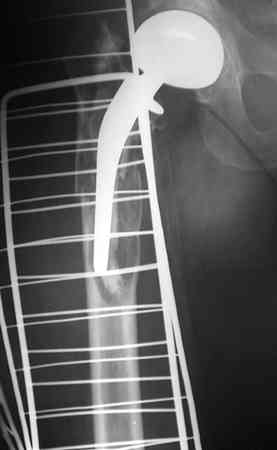

Перелом бедра вокруг эндопротеза

Добрый день! Мужчина, 39 лет., инв. II гр. 27.05.06 получил травму, после неудачного разворота с опорой на ногу почувствовал хруст и резкую боль.

Анамнез: Болеет с 1995 года. В 2000 и 2001 годах произведено тотальное эндопротезирование обоих тазобедренных суставов (сначала левого затем правого). Сейчас в области левого бедра в в/3 имеется резкий отек, боль, крепитация. Диагноз:Состояние после тотального эндопротезирования обеих Т\Б суставов, перелом в/3 левого бедра. Нога уложена на шину Беллера с дисциплинирующим вытяжением. Тактика оперативного лечения?